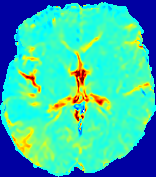

LesionRefer to captionRefer to captionRefer to captionRefer to captionRefer to captionRefer to caption𝐕rgbsubscript𝐕𝑟𝑔𝑏{\bf{V}}_{rgb}Refer to captionRefer to captionRefer to captionRefer to captionRefer to captionRefer to caption𝐕2subscriptnorm𝐕2{\|\bf{V}}\|_{2}Refer to captionRefer to captionRefer to captionRefer to captionRefer to captionRefer to captionRefer to caption3.53.53.52.82.82.82.12.12.11.41.41.40.70.70.70.00.00.0(mm/s)𝑚𝑚𝑠(mm/s)D𝐷DRefer to captionRefer to captionRefer to captionRefer to captionRefer to captionRefer to captionRefer to caption0.0200.0200.0200.0160.0160.0160.0120.0120.0120.0080.0080.0080.0040.0040.0040.0000.0000.000(mm2/s)𝑚superscript𝑚2𝑠(mm^{2}/s)Slice #1Slice #2Slice #3Slice #4Slice #5Slice #6

Figure 4: PIANO feature maps for another patient in the ISLES 2017 training set, where the lesion is located in the right hemisphere. Top row: segmented stroke lesion region (white) on different slices. The corresponding slices for the PIANO feature maps are shown in the following rows.

For a better insight into an estimated velocity field 𝐕𝐕{\bf{V}} and diffusion field 𝐃𝐃{\bf{D}}, we compute the following maps: (1) 𝐕rgbsubscript𝐕𝑟𝑔𝑏{\bf{V}}_{rgb}: Color-coded orientation map of 𝐕=(Vx,Vy,Vz)T𝐕superscriptsuperscript𝑉𝑥superscript𝑉𝑦superscript𝑉𝑧𝑇{\bf{V}}=(V^{x},V^{y},V^{z})^{T}, obtained by normalizing 𝐕𝐕{\bf{V}} to unit length and mapping its 3 components to red, green, blue respectively; (2) 𝐕2subscriptnorm𝐕2\|{\bf{V}}\|_{2}: 222 norm of 𝐕𝐕{\bf{V}}; (3) D𝐷D: scalar field in Eq. 5.

Fig. 3 and Fig. 4 show the PIANO feature maps estimated from two ISLES 2017 patients: all are highly consistent with the lesion in both cases. Details of the blood flow trajectories are revealed in 𝐕rgbsubscript𝐕𝑟𝑔𝑏{\bf{V}}_{rgb} by the ridged patterns and the sharp changes of colors in the unaffected (right) hemisphere, while the flat patterns appearing within the lesion provide little directional information about the velocity and indicate low velocity magnitudes. Velocity magnitudes are more directly visualized via 𝐕2subscriptnorm𝐕2\|{\bf{V}}\|_{2}, from which one can easily locate the lesion where 𝐕2subscriptnorm𝐕2\|{\bf{V}}\|_{2} is low. D𝐷D also indicates lower diffusion values in the lesion, though with less contrast potentially due to the fact that it captures the accumulated effect of CA diffusion at the voxel-level.